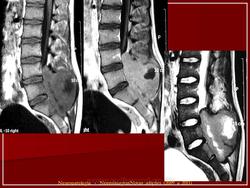

Фиг.1А. -21-летняя женщина с сакральной гигантоклеточной опухолью.

Фиг.1В. -21-летняя женщина с сакральной гигантоклеточной опухолью.